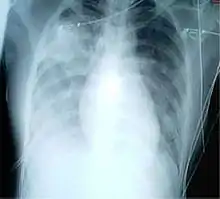

A chest X-ray showing a very prominent wedge-shape area of airspace consolidation in the right lung characteristic of acute bacterial lobar pneumonia.

Consolidation